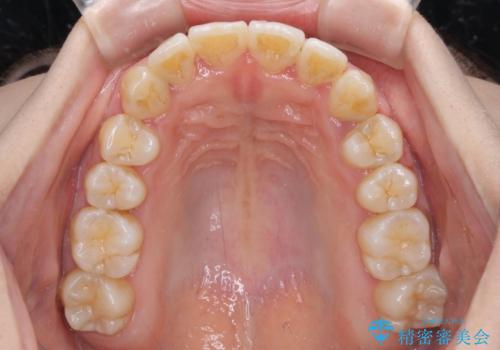

軽微な歯列不正をワイヤー矯正で整える

- 上顎歯列と下顎前歯の叢生を気にして来院された患者様です。

上顎からワイヤー矯正を開始し、終了間際から下顎前歯の叢生解消するよう計画しました。

部分矯正でしたが、咬み合わせに違和感が出ることなく気になる部分を改善させることができました。